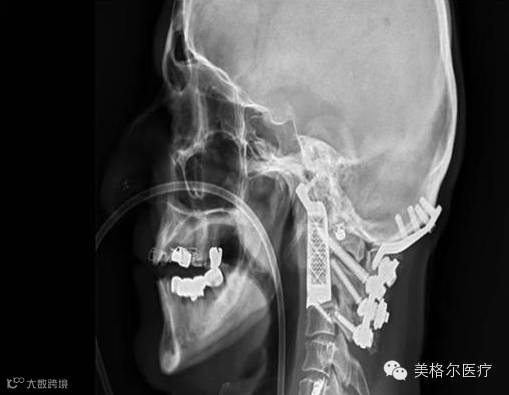

据了解,这位病人名叫Drage Josevski,他患有的是一种非常罕见而难以治疗的脊髓癌——脊索瘤(chordoma)。而且更麻烦的是,X光显示Drage的肿瘤的位置非常危险,该肿瘤处于Drage最上面的两个脊椎上。

为了最大限度地提高手术的成功率,医生们在手术前进行了充分的准备。Mobbs使用计算机模型进行了手术规划。根据计划,外科医生必须从病人的嘴部进入,去除肿瘤以及顶部的两个椎体,并代之以使用钛金属3D打印的身体部位。

Mobbs医生称:“所以我们是从前面完成的颈部肿瘤切除。正如你所称看到的,在取下两个椎体之后,病人的脖子被断开了,但是我们提前准备好了一个完全匹配到位的假体,它像一只手套保持住了脖子和头部交汇处的稳定,以避免他的头掉下来。”

实际上,这次手术是在2015年的12月份完成的,按照Mobbs医生的说法,当时他们成功地拿出了一个非常复杂的肿瘤,而且3D打印部件的植入也很成功,恰到好处地补上了肿瘤留下的空间,非常匹配,总的来说手术很成功。